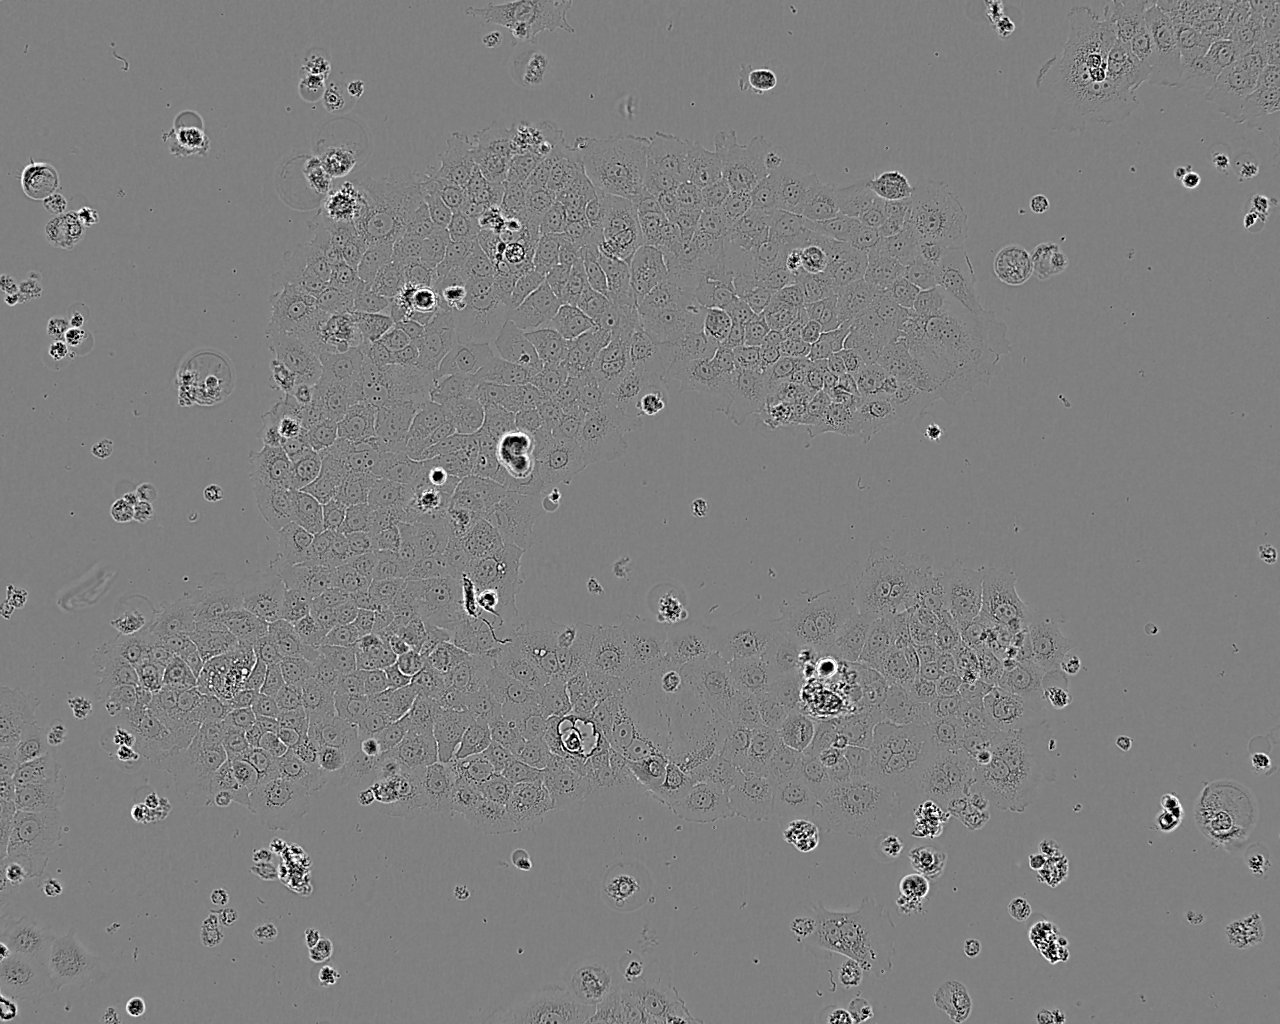

BxPC-3

Derived from a 61 year old female with a primary adenocarcinoma of the pancreas. BxPC-3 cells produce mucin and the tumour produced in a nude mouse is moderately well to poorly differentiated like the primary adenocarcinoma.

Images